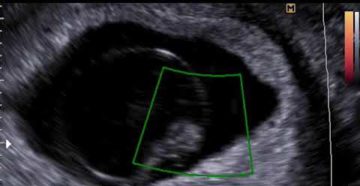

Замершая беременность на ранних сроках: ошибка УЗИ? Замершая беременность (неразвивающаяся, ЗБ) – это гибель плода…